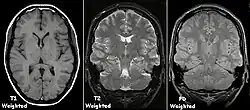

T1 e T2

Cada tecido retorna ao seu estado de equilíbrio após a excitação pelos processos independentes de T1 (spin-tretice) e T2 (spin-spin) de relaxamento. Para criar uma imagem ponderada em T1, a magnetização pode ser recuperada antes de medir o sinal MR, alterando o tempo de repetição (TR). Esta ponderação de imagem é útil para avaliar o córtex cerebral, identificando tecido adiposo, caracterizando lesões focais e, em geral, para obter informações morfológicas, bem como para imagens pós-contraste. Para criar uma imagem ponderada em T2, a magnetização pode decair antes de medir o sinal MR alterando o tempo de eco (TE). Esta ponderação de imagem é útil para detectar edema e inflamação, revelando lesões de substância branca e avaliando a anatomia zonal na próstata e no útero.

A exibição padrão de imagens de MRI é representar características de fluido em imagens em preto e branco, onde diferentes tecidos são os seguintes: